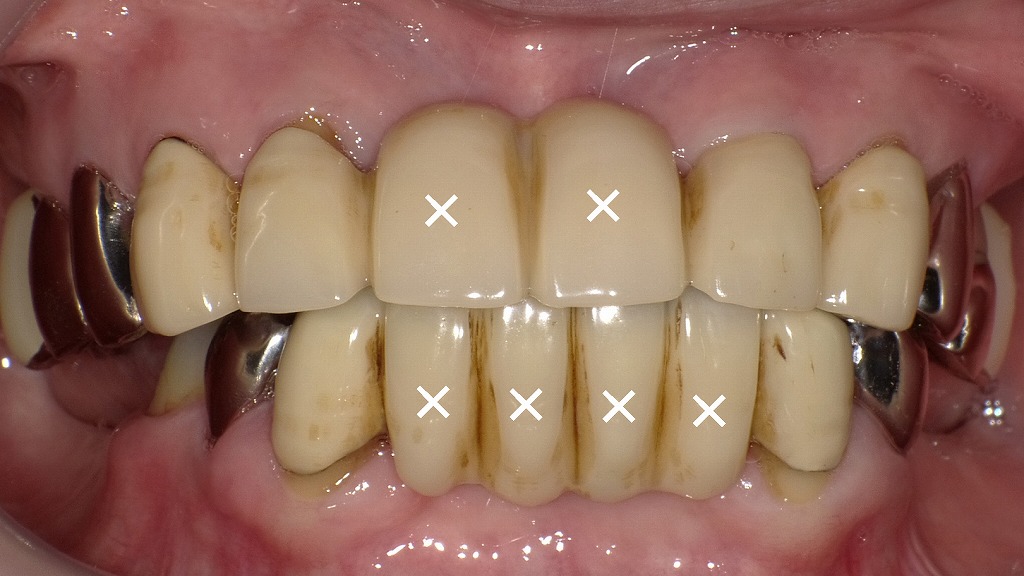

保険の硬質レジン前装冠ブリッジの見た目と審美性の限界(欠損部×印)

保険適用の硬質レジン前装冠ブリッジは、費用を抑えながら白い歯を再現できる治療法ですが、経年的な変色や摩耗が起こりやすく、自然な透明感や色調の再現には制約があります。

画像の×印は欠損部を示しており、広範囲の欠損をブリッジで補う場合、見た目の不調和だけでなく支台歯への負担増加も問題となりやすい点です。

審美性や耐久性を重視する場合は、ジルコニアなど保険外の素材を選択することで、より自然で長持ちする結果が期待できます。